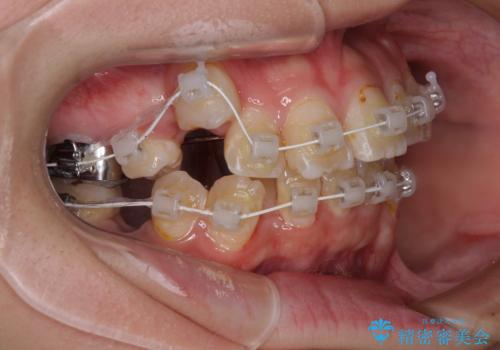

- 矯正装置

- 審美装置

重度叢生のため、大臼歯をしっかりと咬合させるために、下顎は左右第二小臼歯を、上顎は前歯部の叢生を解消するために左右第一小臼歯を抜歯し、口元の突出感を改善するために、上顎大臼歯が前方に移動しないようにするために、補助装置による架強固定を行うこととしました。

叢生は思ったよりも早期に改善されましたが、舌の突出癖による上下前歯の非接触が全く改善されず、2年間ほど治療期間が延びる結果となってしまいました。